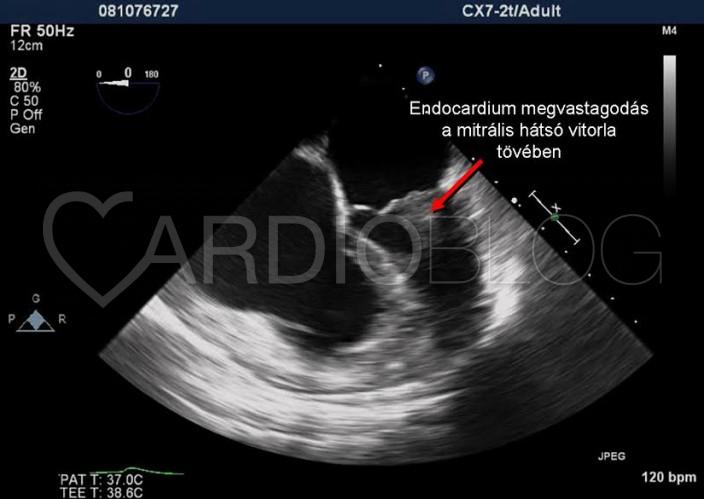

Ezen kívül megvastagodott az endocardium a bal kamrában a mitrális hátsó vitorla alatt (4. ábra), II. fokú regurgitációt okozva (ezt TEE vizsgálattal is megerősítettük, 3. videó).

Az elvégzett MRI vizsgálat normális bal és jobb kamrai volumeneket és ejekciós frakciókat írt le, jobb kamra csúcsi és bal kamra subvalvuláris endocardium megvastagodással, mely Löffler kórnak megfelel. A beteg panaszai és a látott kép alapján felmerült a sebészi endocardiectomia lehetősége (a megvastagodott, fibrotikus endocardium „lehámozása”), további kivizsgálásig a beteget hazaengedtük.

A Löffler kór a hypereosinophil szindróma kardiális manifesztációja, ami endomyocardiális fibrosis révén restriktív cardiomyopathiát okoz. Főként a kamrák csúcsi része, és a subvalvularis régió érintett. Ha a kamracsúcs érintett, gyakran látható benne thrombus. Tünetei lehet a jobb, illetve balszívfél elégtelenség, mitrális regurgitáció, szisztémás

embolizáció. Echocardiográfiával látható a megvastagodott endocardium, a csúcsi thrombus, restriktív diasztolés diszfunkció, mitrális, vagy tricuspidális regurgitáció. Gyógyszeres kezelésében corticosteroid, hidroxyurea és infterferon terápia jön szóba, thrombus esetén anticoagulálás szükséges. Gyógyszeres kezelés hatástalansága és progrediáló szívelégtelenség esetén sebészi endocardiectomia jön szóba.